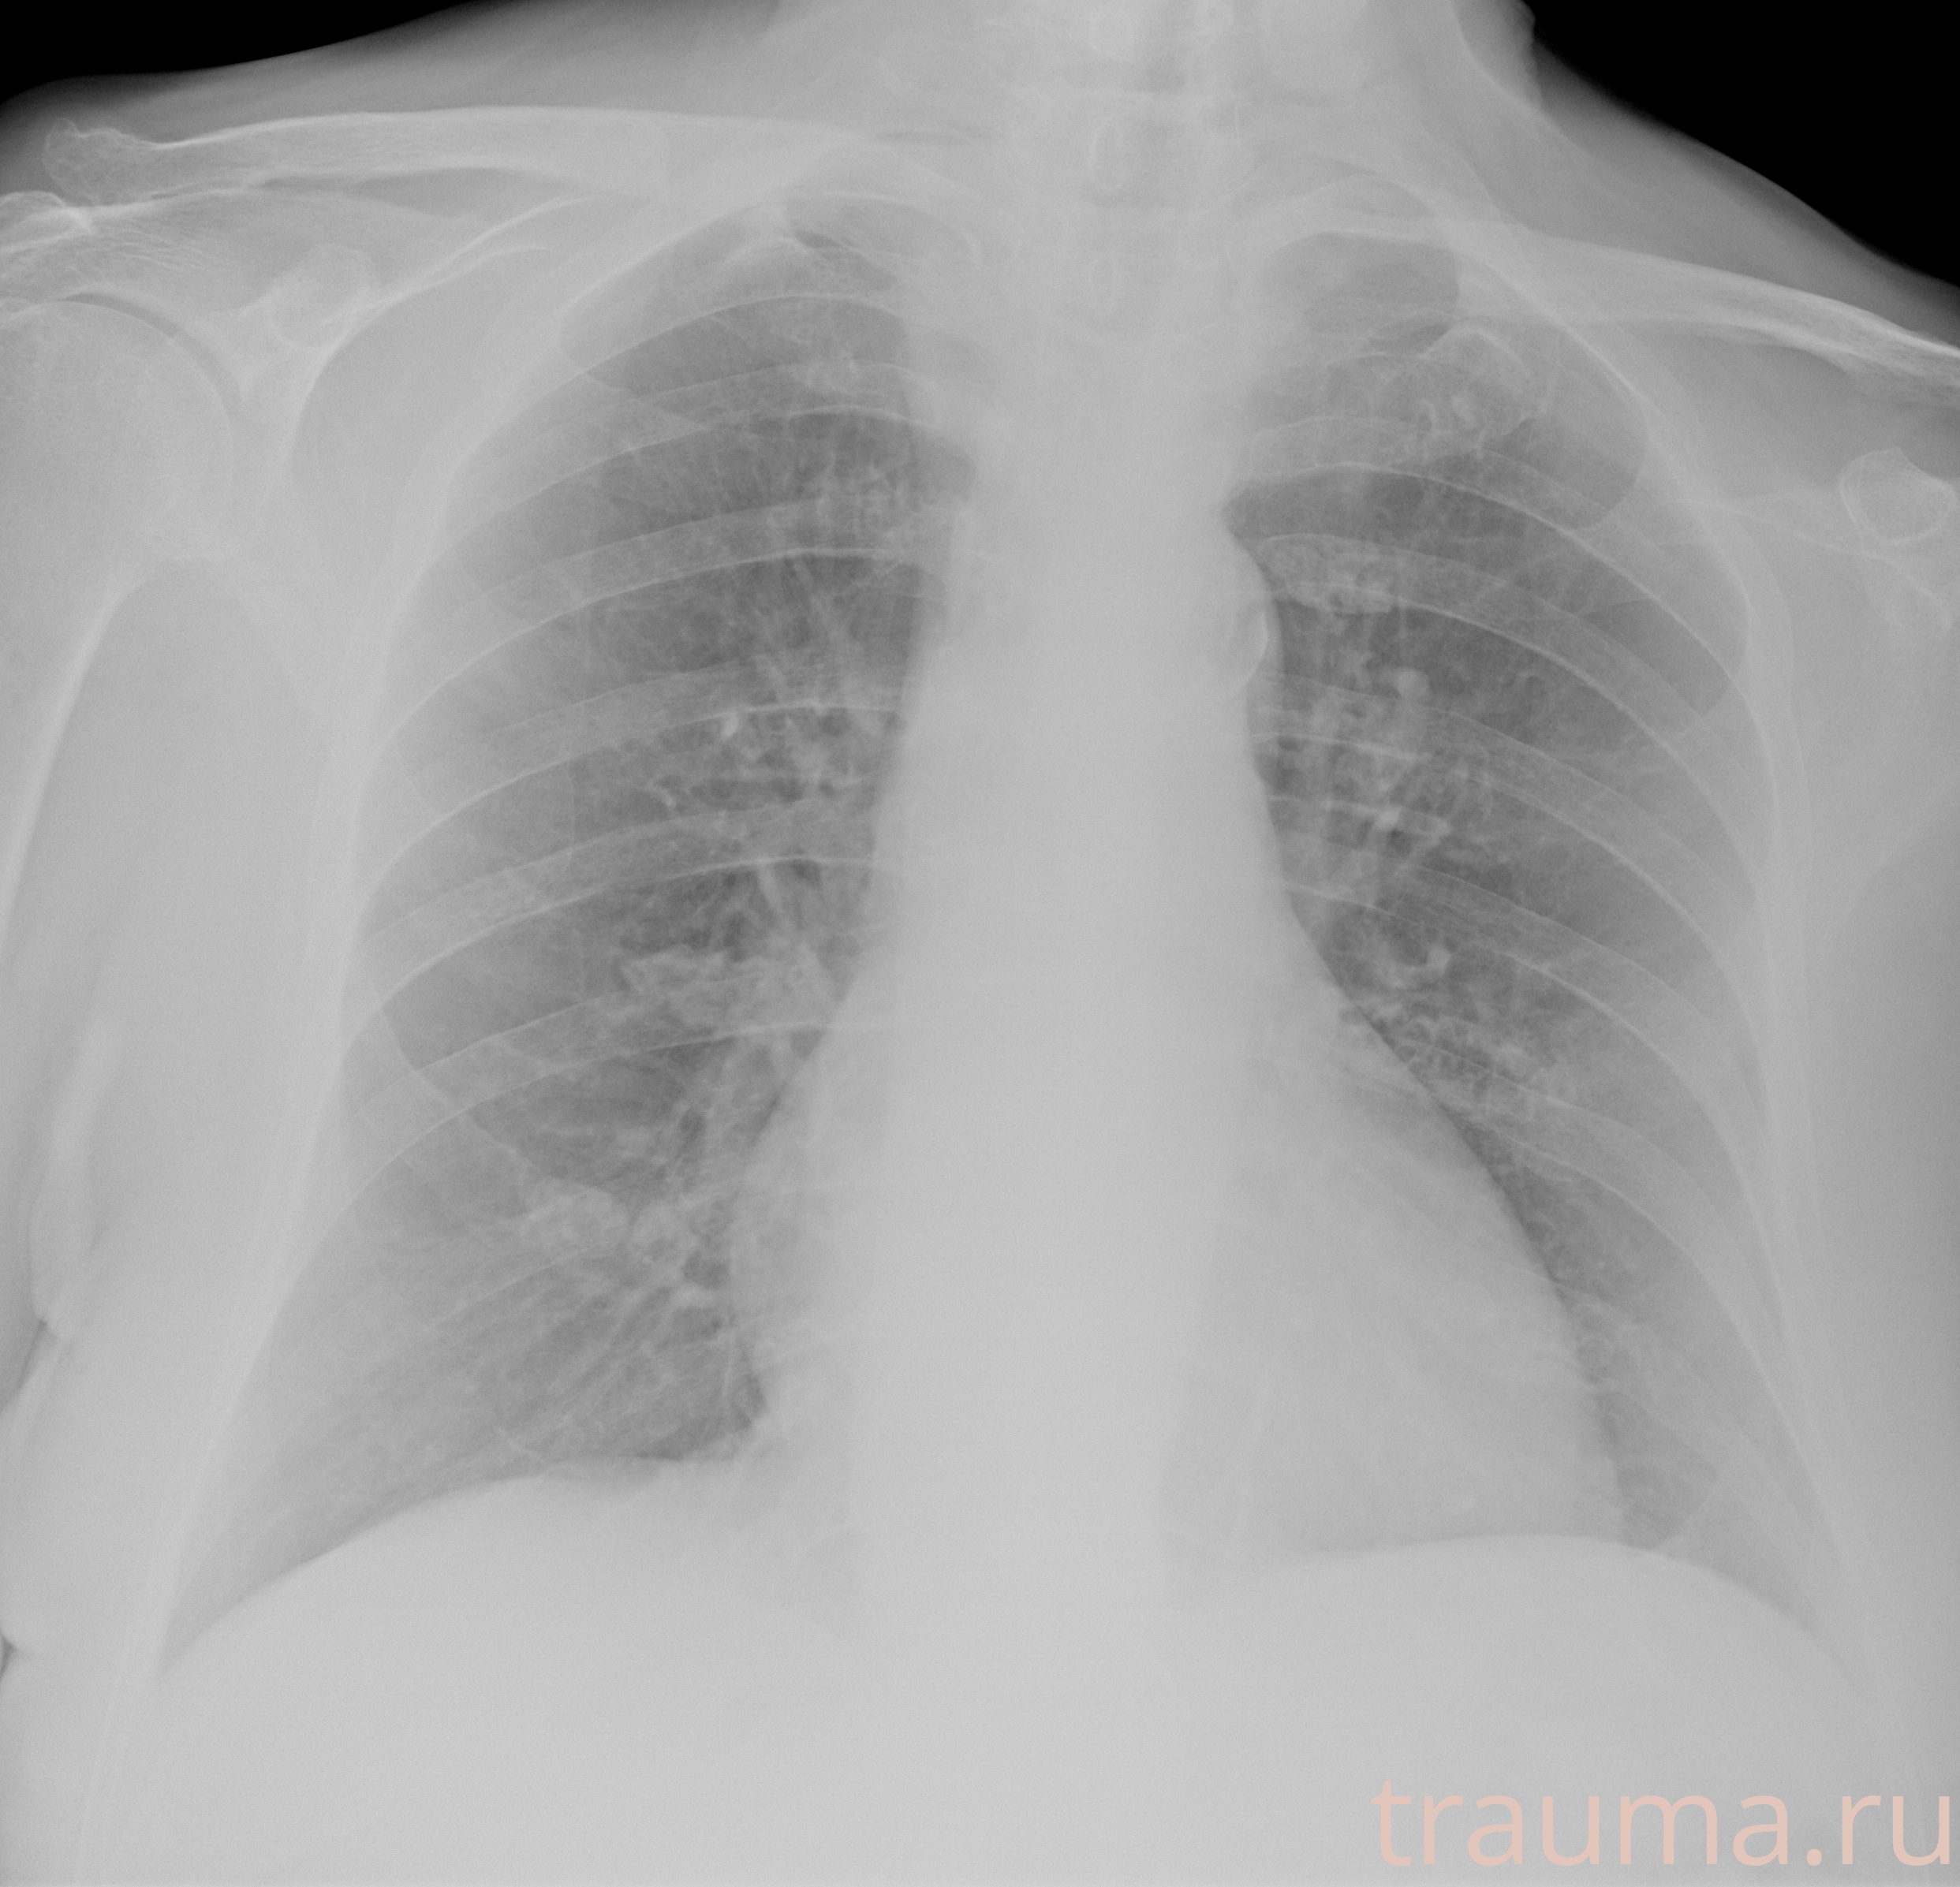

Рентгенограммы

Рентген на дому: по вашему адресу приезжает врач-рентгенолог, травматолог-ортопед с мобильным рентгеновским аппаратом, проводит диагностику травмы или заболевания, делает необходимые рентгенограммы, дает рекомендации по дальнейшему лечению. Получить качественные снимки в домашних условиях возможно благодаря уникальной методике, разработанной МосРентген Центром для института  Склифосовского